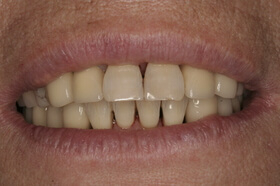

A fogágybetegség kezelése után a beteg fogszabályozó készüléket kap az esztétikai eltérés korrekciójára

A kezelés végén a fogszabályozó készülék eltávolítása előtt

A végeredmény, a frontfogak a belső oldalon összesínezve